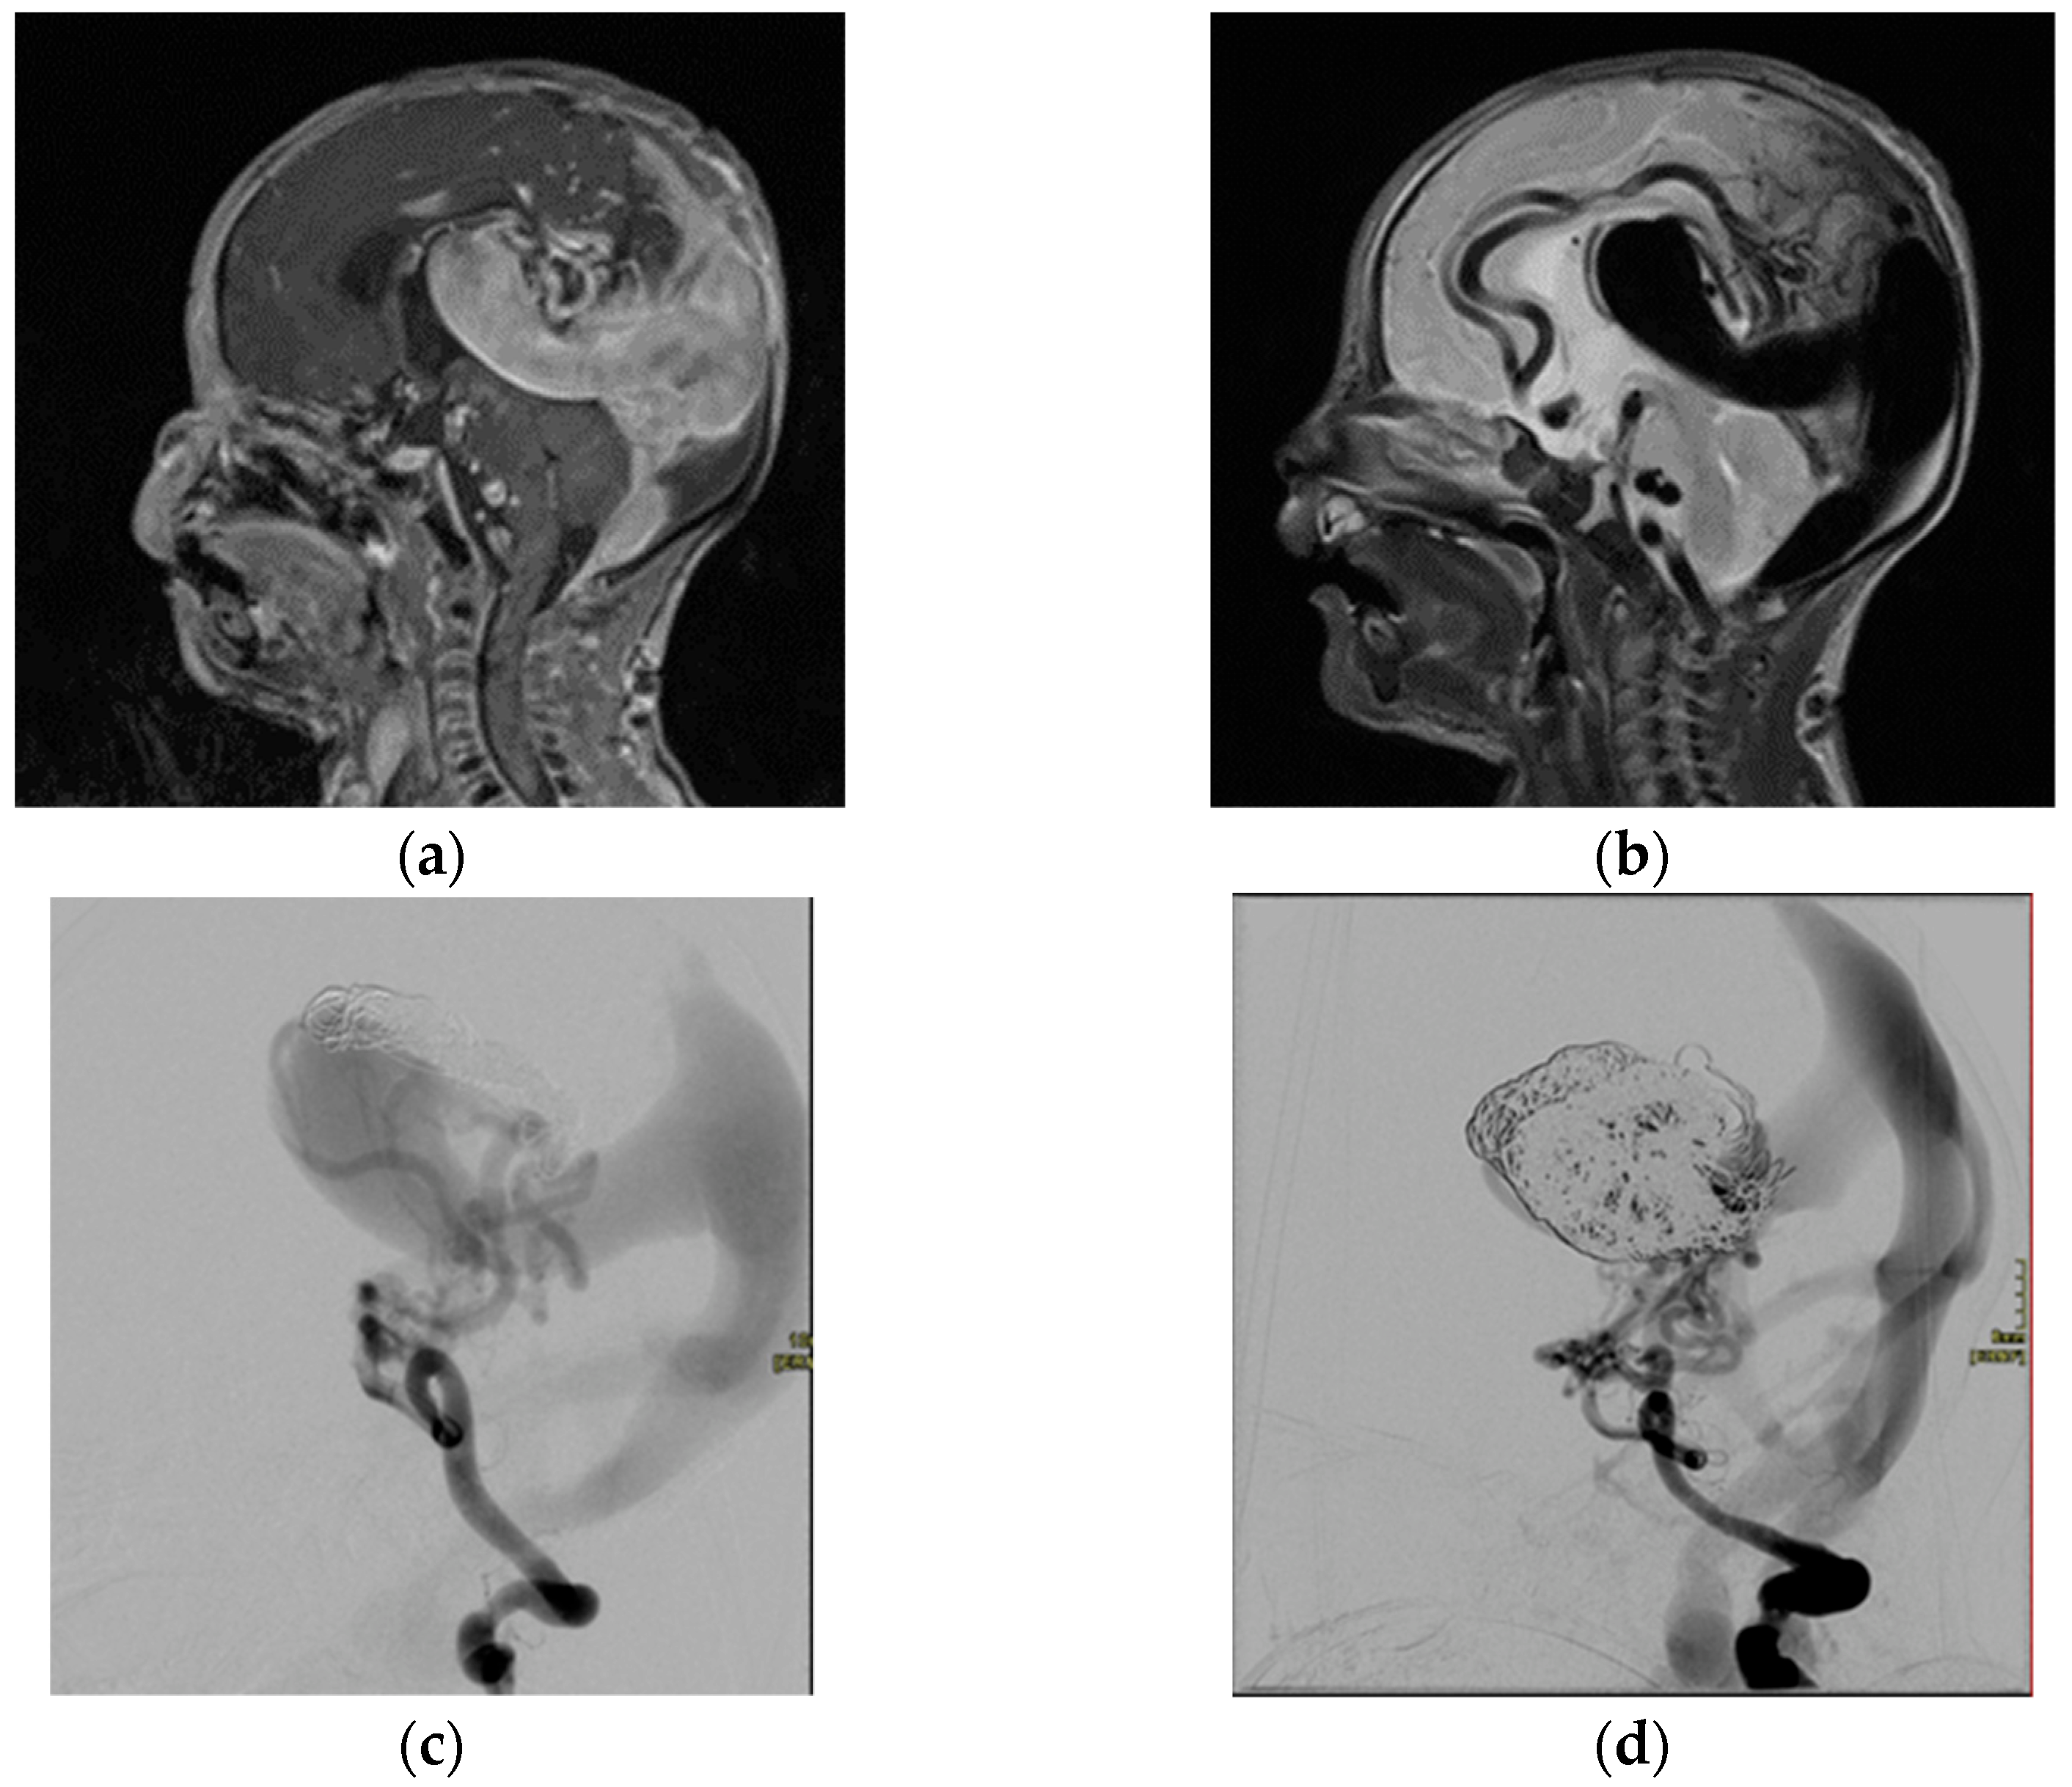

2.1.2. Vein of Galen Malformation